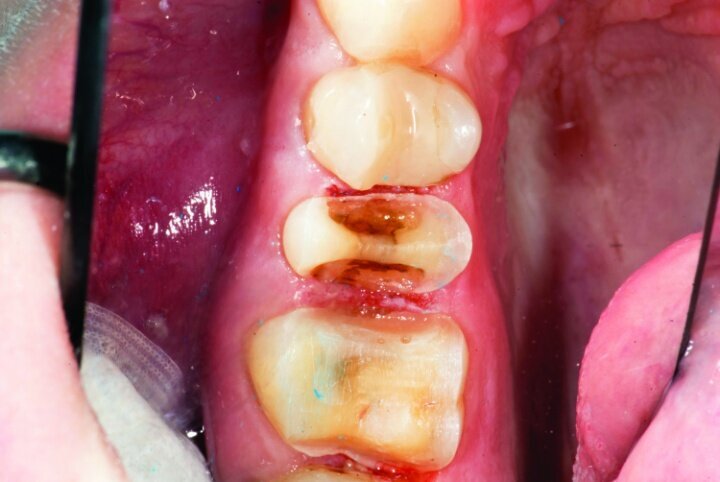

The remainder of the existing composite resin in #3 and the amalgam in #4 were removed. The occlusal surfaces of the preparations were blended into the interproximal areas using a KS2 bur to create smooth preparations (Figs. 10–15c). There was no retention or resistance form prepared to retain the restorations.

Tissue management was obtained with ViscoStat Clear, gingival haemostatic gel, 25 percent (m/m) aluminum chloride (Figs. 16 & 17). Gingival retraction was obtained using a two-cord system. First, a #00 size cord from Ultradent was placed on the mesial and distal of both preparations (Figs. 18 & 19).